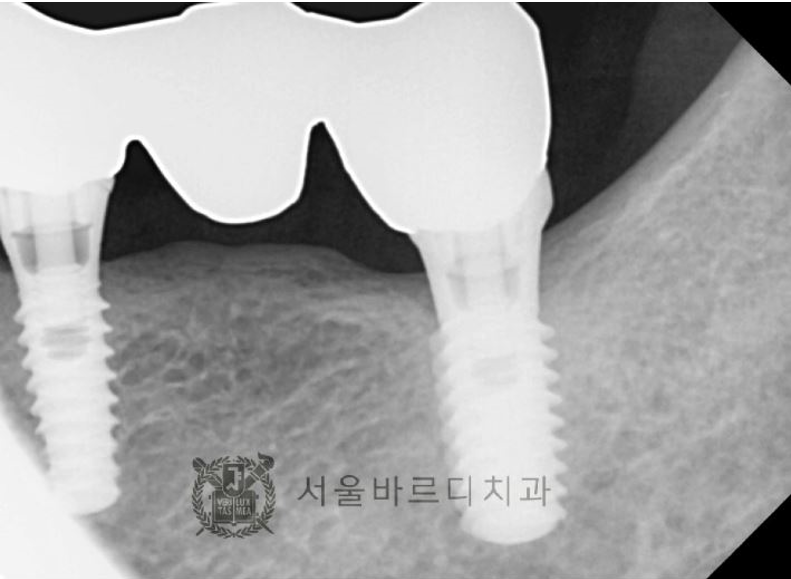

임플란트 2개로 4개의 치아를 만들어 놓은 브릿지인데…

사진상으로도 뼈소실이 많이 있었고,

심하게 흔들리는 상태이셨는데 자연적으로 빠지셨습니다.

앞에 임플란트(작은 어금니)의 뿌리 부분의 뼈가 염증으로 녹아

더 이상 임플란트가 뼈에 박혀 있을 수 없어서

뒤 보철물과 함께 빠진 경우입니다.

그나마 끝 어금니(큰어금니)가 잡아주고 있어서

지금까지 사용이 가능했으나

끝 어금니 임플란트의 나사가 풀리면서

보철물이 빠지게 된 것입니다..